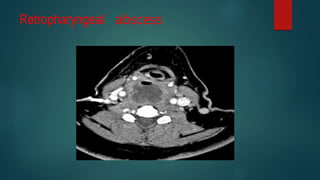

Retropharyngeal abscess

• #128 Annotations showing the normal width of the pre-vertebral soft tissue at the various cervical levels. The annotated pathological images reveals the magnitude of the soft tissue widening.

• #129 Huge fluid-gas filled rim enhancing abscess in the retropharyngeal space. Its extends over nearly the whole length of the cervical spine.